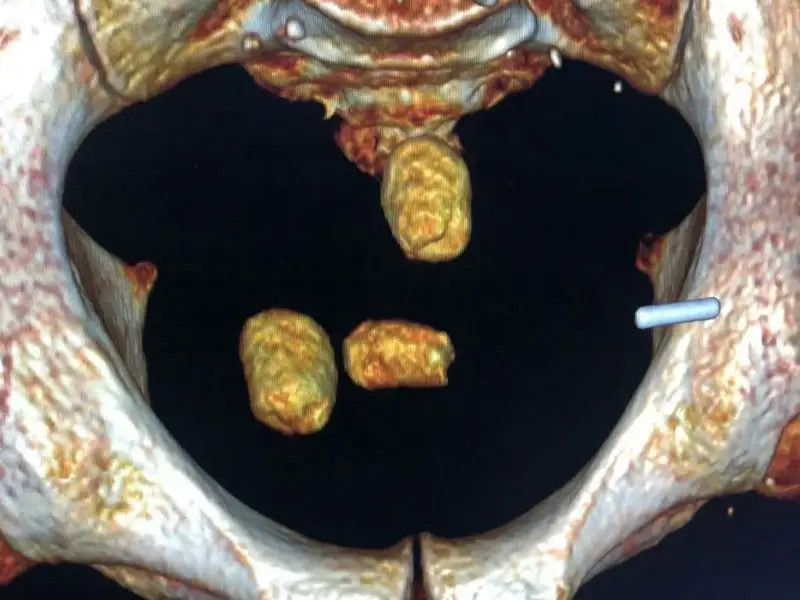

Рентгеноскопиялық зерттеу олардың іш қуысында бөгде заттың барын көрсетті.

Арнайы медициналық процедура арқылы шетелдіктердің асқазанынан героин және синтетикалық есірткі бар 30-дан астам контейнер алынды.

Алынған заттың жалпы салмағы шамамен 1 кг болды.